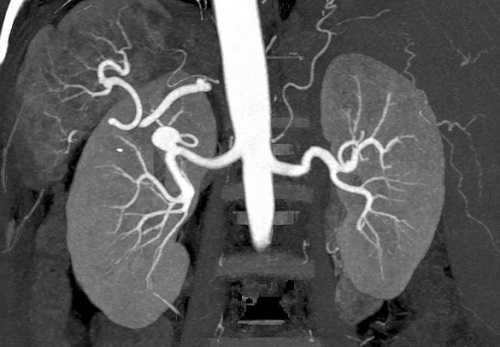

КТА отражает особенности строения вен и артерий головного мозга, легких, внутренних органов, периферических сосудов верхних и нижних конечностей. При проведении КТ ангиографии изучают состояние аорты, оценивают характер коронарного кровоснабжения.

Контрастная КТ ангиография почечных артерий

При наличии аневризмы раствор заполняет патологический карман, показывает расположение и размеры очага.